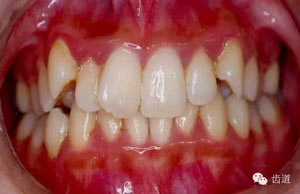

5.齲齒、牙周病及口腔衛(wèi)生情況。

45.webp.jpg